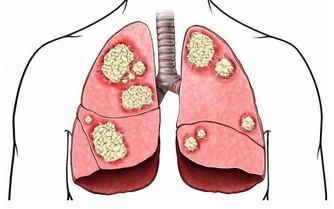

五.總是拖著長長的鼻涕說話時鼻音重,睡眠時鼻子不通氣,呼嚕響亮,且總長不胖,要當心腺樣體肥大。